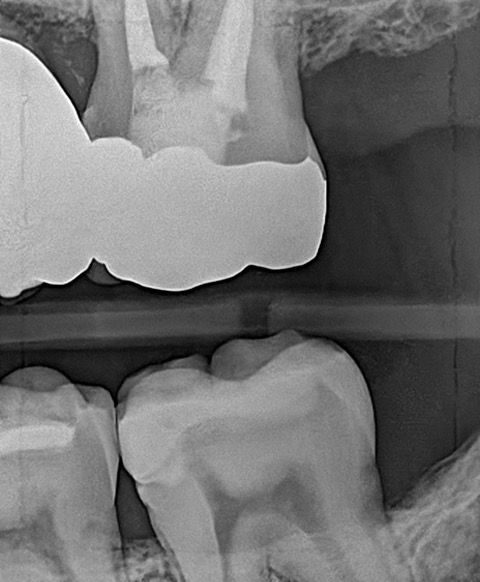

In my own practice, I compared two bitewings from the same patient, one taken with Acuity and one with our existing sensor, using identical exposure settings. The Acuity image immediately stood out. It showed noticeably sharper definition, cleaner contrast, and clearer interproximal visibility. The improvement was visible at a glance and reinforced the diagnostic advantages reported by our evaluators. This kind of image sharpness saves time and reduces retakes.